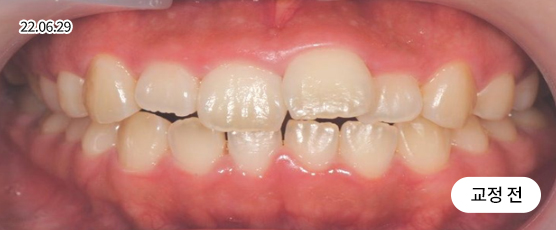

매복치 Solution

매복치는 잇몸 속에서 인접 치아에 손상을 줄 수 있어

치아 견인을 통해 제자리를 찾아주어야 정상적으로 치아가 자리 잡을 수 있습니다.

* 치근흡수, 잇몸퇴축 등 부작용이 발생할 수 있습니다.

* 본 사진은 동일 조건에서 촬영되었으며, 환자 본인의 동의를 얻어 게재되었습니다.